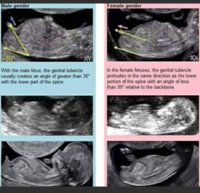

No siis se Googlesta löytyvä tosi varma sukupuolen ennustamisjuttu.:hilarious::angelic: Tai en mä tiedä vaikka olisikin ammattilaisen käyttämänä varmempi.

Että jos sikiöllä on uloke ”pippeli” alaspäin, niin tarkoittaa tyttöä. Ja ”pippeli” ylöspäin tarkoittaa poikaa.